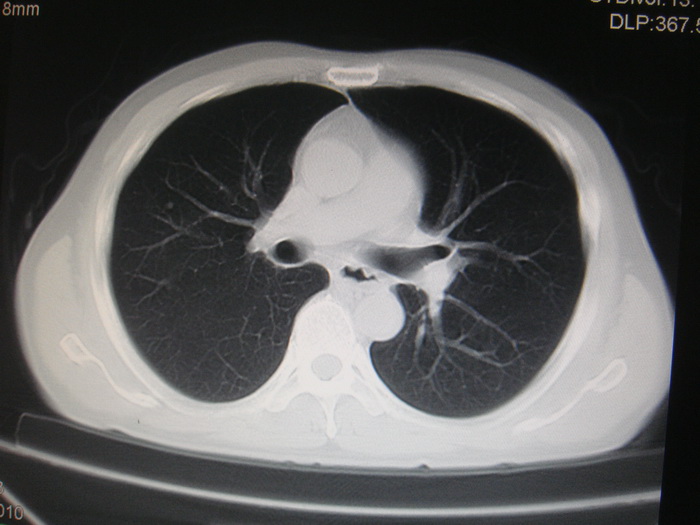

标题: CT28366:男性,45岁,偶尔发现右颈部肿块行胸部CT扫描。 [打印本页]

男性,45岁,偶尔发现右颈部肿块行胸部ct扫描。

两肺多发结节灶及纵膈淋巴结肿大考虑为转移

两肺多发性转移瘤,纵隔淋巴结转移。

两肺多发性转移瘤,纵隔淋巴结转移。食道中上段管壁似乎增厚,作相关检查。

两肺多发性转移瘤,前上纵隔淋巴结转移。